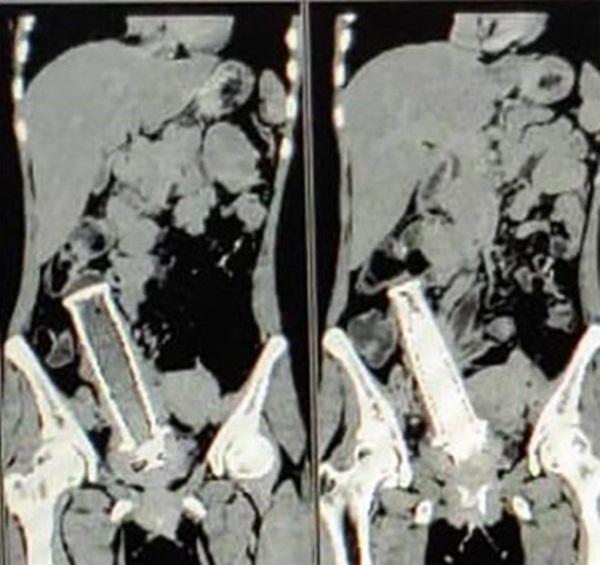

Các bác sĩ đã quét cơ thể cô bằng CT và kinh hoàng phát hiện ra có một vật thể lạ tương đối lớn nằm trong tử cung của cô.

Theo Mstar, người phụ nữ 30 tuổi này đã được đưa đi cấp cứu tại Bệnh viên MY sau khi cảm thấy bị đau bụng dữ dội. Các bác sĩ đã quét cơ thể cô bằng CT và kinh hoàng phát hiện ra có một vật thể lạ tương đối lớn nằm trong tử cung của cô.

Trải qua thêm vài lần quét nữa, vật thể bí ẩn đó được xác định là một tay cầm xe máy. Người phụ nữ này ngay lập tức được đưa vào phòng mổ, 19 bác sĩ đã thay phiên nhau lấy dị vật trong ca phẫu thuật kéo dài 4 giờ đồng hồ.